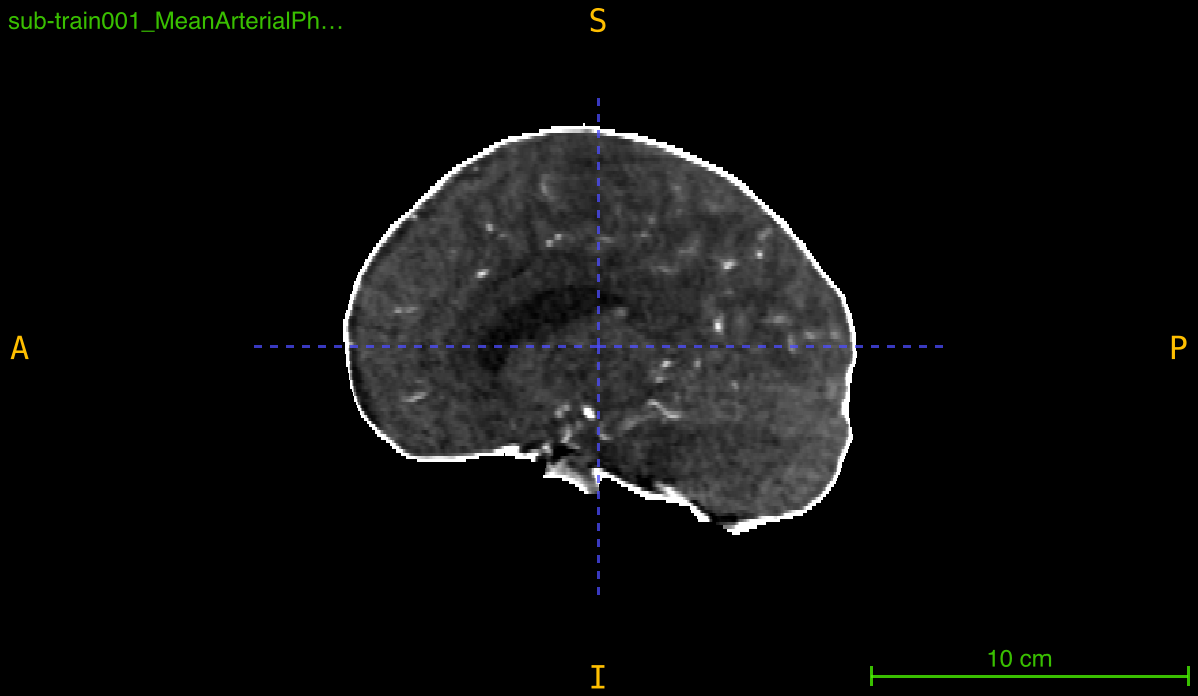

Creating Visualization Overlay

Generate mask overlay for quality inspection: